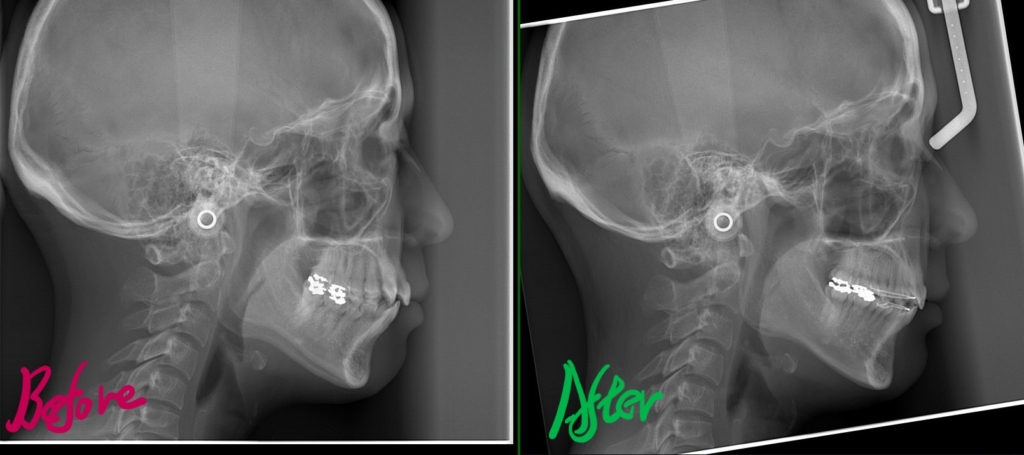

レントゲン写真でも矯正治療前後を比較してみましょう

上のレントゲン写真で見るよりも、顔写真で見る方が矯正後の口元がスッキリしたことが分かります

口元がスッキリして、オトガイにあった梅干し状のシワもほぼ無くなりました